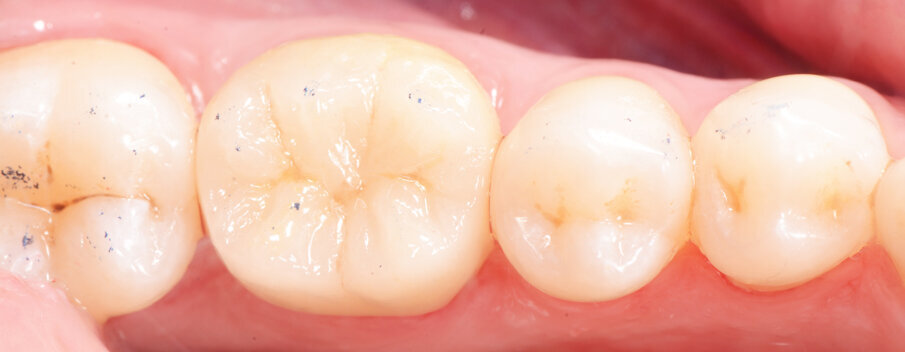

Fig. 11: Seated crown after excess removal

Fig. 12a: Lateral and occlusal view of the completed restoration

Fig. 12b: Lateral and occlusal view of the completed restoration

The adhesive (Tetric N-Bond Universal) was applied and dispersed with a strong stream of air. The dual-curing (DC) version of the Variolink Esthetic luting composite was used for seating due to the thickness of the crown and the low translucency of the ceramic material (Fig. 7). The luting composite was applied into the crown. Then the restoration was seated (Fig. 8) and light cured from each side for two seconds. Excess composite was easy to remove due to the Ivocerin photoinitiator, which provides a fast and thorough cure with a minimum amount of energy (Fig. 9). For final polymerization, the restoration was light-cured from each quarter for 20 seconds (Fig. 10). Figure 11 shows the oral situation after placement of the crown. Although the cement line is located above the gingival margin, it is not visible due to the favourable tone and opacity of the luting composite. Fig. 12 shows an X-ray control image of the restoration: the radiopaque build-up material and cement can be easily told from the tooth structure. This aspect is particularly important in situation where excess cement cannot be seen with the naked eye.